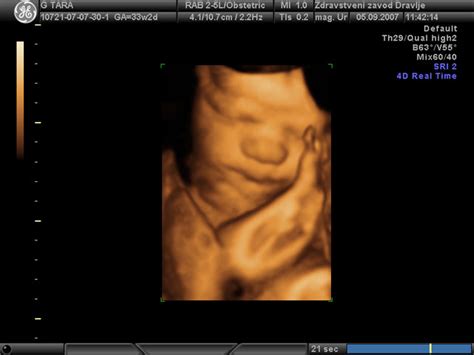

Med nosečnostjo ultrazvočni pregledi postanejo ključno orodje za spremljanje rasti in razvoja ploda. S pomočjo ultrazvoka lahko zdravniki izmerijo različne parametre, kot so:

- BPD (Biparietalni premer): Meritev premera glave otroka.

- AC (Abdominalni obseg): Meritev obsega trebuščka otroka.

- FL (Femourna dolžina): Dolžina stegnenice.

- Teža: Ocena telesne teže otroka, ki se izračuna na podlagi drugih meritev.

- AFI (Amniotic Fluid Index): Indeks plodovnice, ki meri količino plodovnice v maternici.

V primeru, ko je nosečnica v 31. tednu in 5. dnevu nosečnosti, so bile izmerjene naslednje vrednosti: S/F: 30 cm, BPD: 81 mm, AC: 315 mm, teža: 2400 - 2500 g, AFI: 21, pretoki: 0,55. Te mere kažejo, da je plod med večjimi. Na primer, BPD 81 mm v 31. tednu in 5. dnevu nosečnosti je lahko na zgornji meji normale ali nekoliko nad njo, kar nakazuje na večjo glavo. Obseg trebuščka (AC) 315 mm v istem obdobju prav tako nakazuje na večji plod. Zlasti, če je otrok do 24. tedna ustrezal pričakovanim meram, nato pa se je rast pospešila, je to lahko opazno.